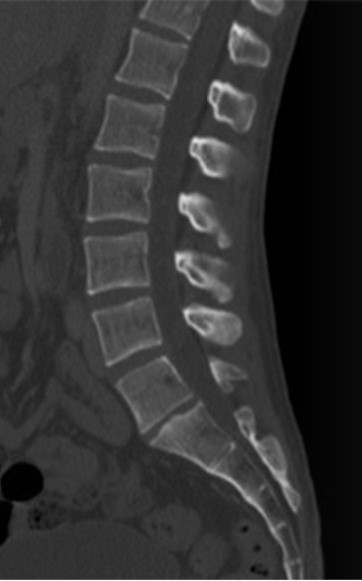

Które kolejne sekwencje badania kręgosłupa lędźwiowego uwidoczniono na przedstawionych obrazach?

A. Sag T2, Sag STIR, Sag T1

B. Sag STIR, Sag T2, Sag T1

C. Sag T2, Sag T1, Sag STIR

D. Sag T1, Sag STIR, Sag T2